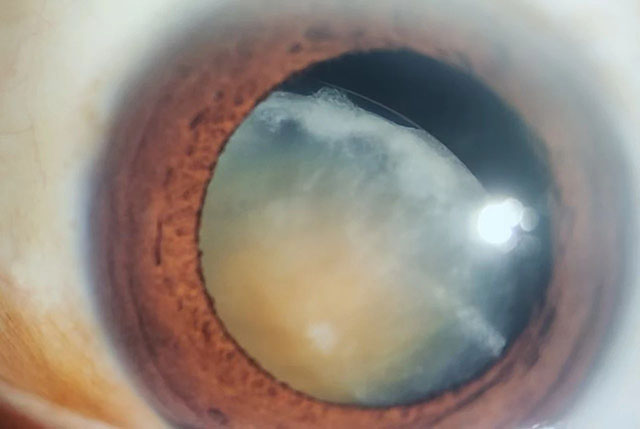

晶体半脱位患者的眼前段相片

援疆医生与深圳市眼科医院专家一起会诊,最后确诊为晶状体半脱位,并进一步商讨手术治疗方案。

第二天,这例疑难复杂的患者由深圳市眼科专家团队在喀什市人民医院顺利完成了晶状体的摘除联合前段玻璃体切除术和晶状体悬吊术。